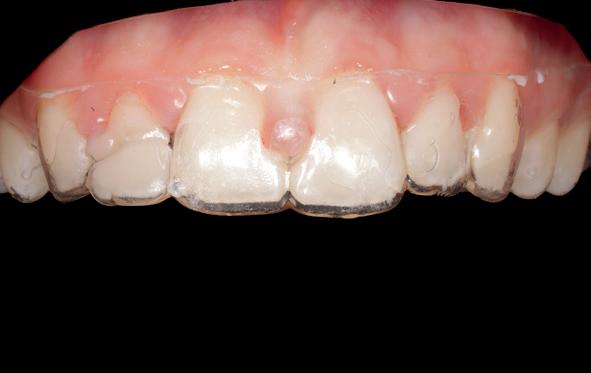

Na het reponeren en voorafgaand aan fixatie van de 11 en 21, heb ik de positie getoetst middels een nieuwe matching (afbeelding 8-9). Hieruit bleek dat 11 en 21 nog iets geïnclineerd moesten worden. Tijdens

het uitharden is er nog druk uitgeoefend op deze elementen om de laatste puntjes op de i te zetten. Daarna is de lip gehecht (afbeelding 10-14).